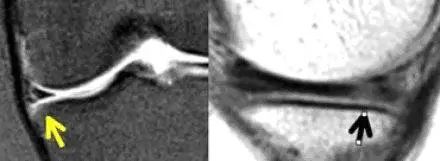

图 4 半月板横韧带

左图:横断面 T1 像显示半月板横韧带连接内侧半月板(白色圆箭头)和外侧半月板(白色直箭头)的前角;右图:经过半月板横韧带(黑色箭头)的矢状面,可见半月板横韧带与半月板前角之间的间隙呈现高信号(白色箭头),易误诊为半月板撕裂。